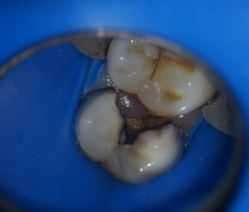

Пример осложненного кариеса контактной поверхности , в данном случае потребуется лечение корневых каналов зуба ,укрепление зуба штифтом и последующие покрытие зуба коронкой. Вот такой печальный итог небрежного отношения к своему здоровью.

Видна значительная потеря твердых тканей зуба в результате кариозного процесса и как следствие необходимость сложного и затратного лечения.